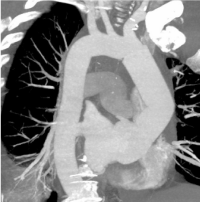

Initially, during the existing strategy, it was planned to apply a clamp directly in front of the brachiocephalic trunk's orifice, but, taking into account the MRI data, the surgical approach was adjusted. Considering the spread of the lesion of the aortic wall to the arcus distal to the aneurysm, it was decided to perform the intervention under conditions of circulatory arrest and antegrade unilateral cerebral perfusion. It is important that in case of resection and the pathology altered aortic wall, complications can be expected in the early and the late postoperative period. In this case, the patient underwent supracoronary prosthesis of the ascending part and the aortic arch with the formation of a distal anastomosis of the "half-arc" type.

After surgical treatment, a CT angiographic of the thoracic aorta was performed (Figure 5). On postoperative scans, the diameter of the contrasting lumen of the aorta was not expanded. There were no endolics.

Figure 5. CT angiography of the thoracic aorta after surgical treatment